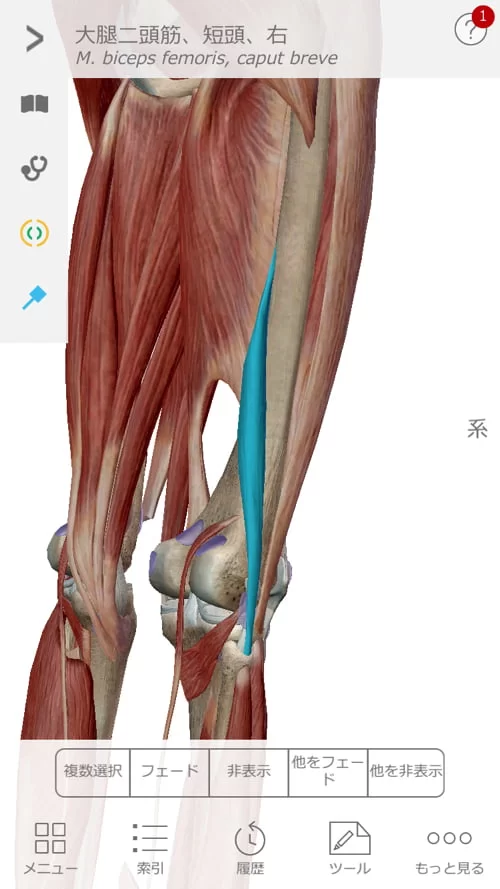

それから骨盤から膝に繋がる筋肉。

そして膝から足の裏に繋がる筋肉。